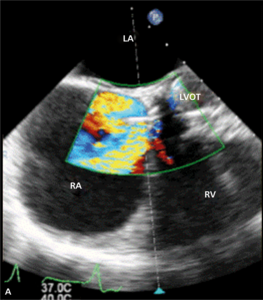

Rycina 4. Wynik przezskórnego leczenia defektu Gerbode w trójwymiarowej echokardiografii przezprzełykowej [A], w 64-rzędowej tomografii komputerowej [B].

W badaniu echokardiograficznym może dojść do omyłkowej interpretacji strumienia przecieku do prawego przedsionka jako fali zwrotnej przez zastawkę trójdzielną, a w konsekwencji do rozpoznania ciężkiego nadciśnienia płucnego [28]. Pomocą we właściwej interpretacji uzyskanego obrazu może być echokardiografia trójwymiarowa czasu rzeczywistego [29].

Leczenie zabiegowe nabytej wady typu Gerbode to przede wszystkim ponowny zabieg kardiochirurgiczny. Szacowana na podstawie danych sprzed kilkudziesięciu lat śmiertelność okołozabiegowa wynosi około 16% [25]. Gdy nie ma aktywnego zapalenia wsierdzia i przy współistnieniu korzystnych warunków anatomicznych możliwe jest również przezskórne zamknięcie ubytku. Zastosowanie znalazły tutaj zapinki do mięśniowego VSD [30], ubytku w przegrodzie międzyprzedsionkowej (atrial septal defect, ASD) [31] czy PDA [32]. W ośrodku autorów do zamknięcia tego typu ubytku u chorego po AVR (zastawka Sorin Pericarbon) użyto zatyczki dedykowanej do okołobłoniastego VSD (perimembranous VSC, pmVSD), uzyskując pełne zamknięcie ubytku (ryc. 3, 4). Podobnie jak w przypadku innych implantacji zatyczek w okolicę mechanicznej zastawki serca, podstawowym problemem jest taki dobór urządzenia, aby zminimalizować prawdopodobieństwo zablokowania dysków zastawki przy jednocześnie możliwie całkowitym wypełnieniu ubytku.